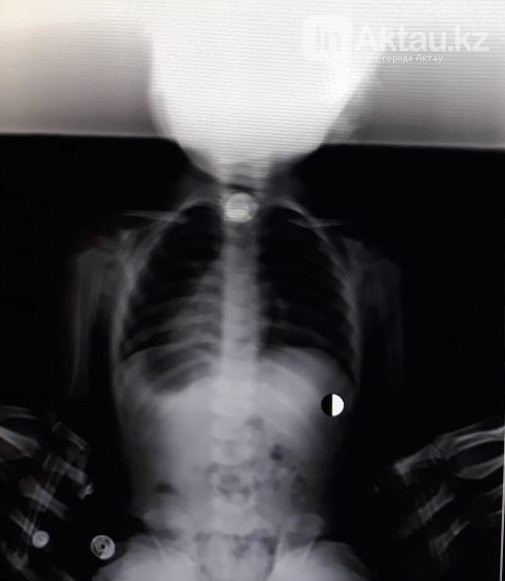

Девочку с жалобами на затрудненное дыхание доставили в приемный покой Бейнеуской ЦРБ 18 марта. Сделав рентген, медики обнаружили в дыхательных путях ребенка инородный предмет.

По словам врачей, они решили не дожидаться отправки девочки в областную детскую больницу и попытались очистить дыхательные пути ребенка самостоятельно. "Врачи приняли решение вытаскивать инородный предмет, используя опыт испанских врачей, который, по словам директора Бейнеуской ЦРБ, он получил у заграничных коллег. Из дыхательных путей девочки врачи извлекли 10-тенговую монету. В настоящее время здоровью маленькой пациентки ничего не угрожает", - рассказали в пресс-службе облздрава.